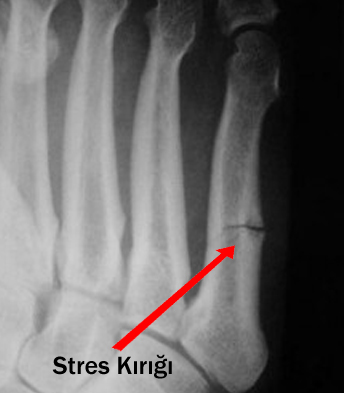

Stres kırığı tanısı nasıl konur?

Normal kırıklardan farklı olarak, stres kırığında kırık hattı çok ince çatlak şeklinde olduğu için röntgenle tanı koymak her zaman mümkün olmaz. Stres kırığı tanısı bazen gözden kaçabilir.  Kırktan şüphelenilen durumlarda MRI çekilmelidir